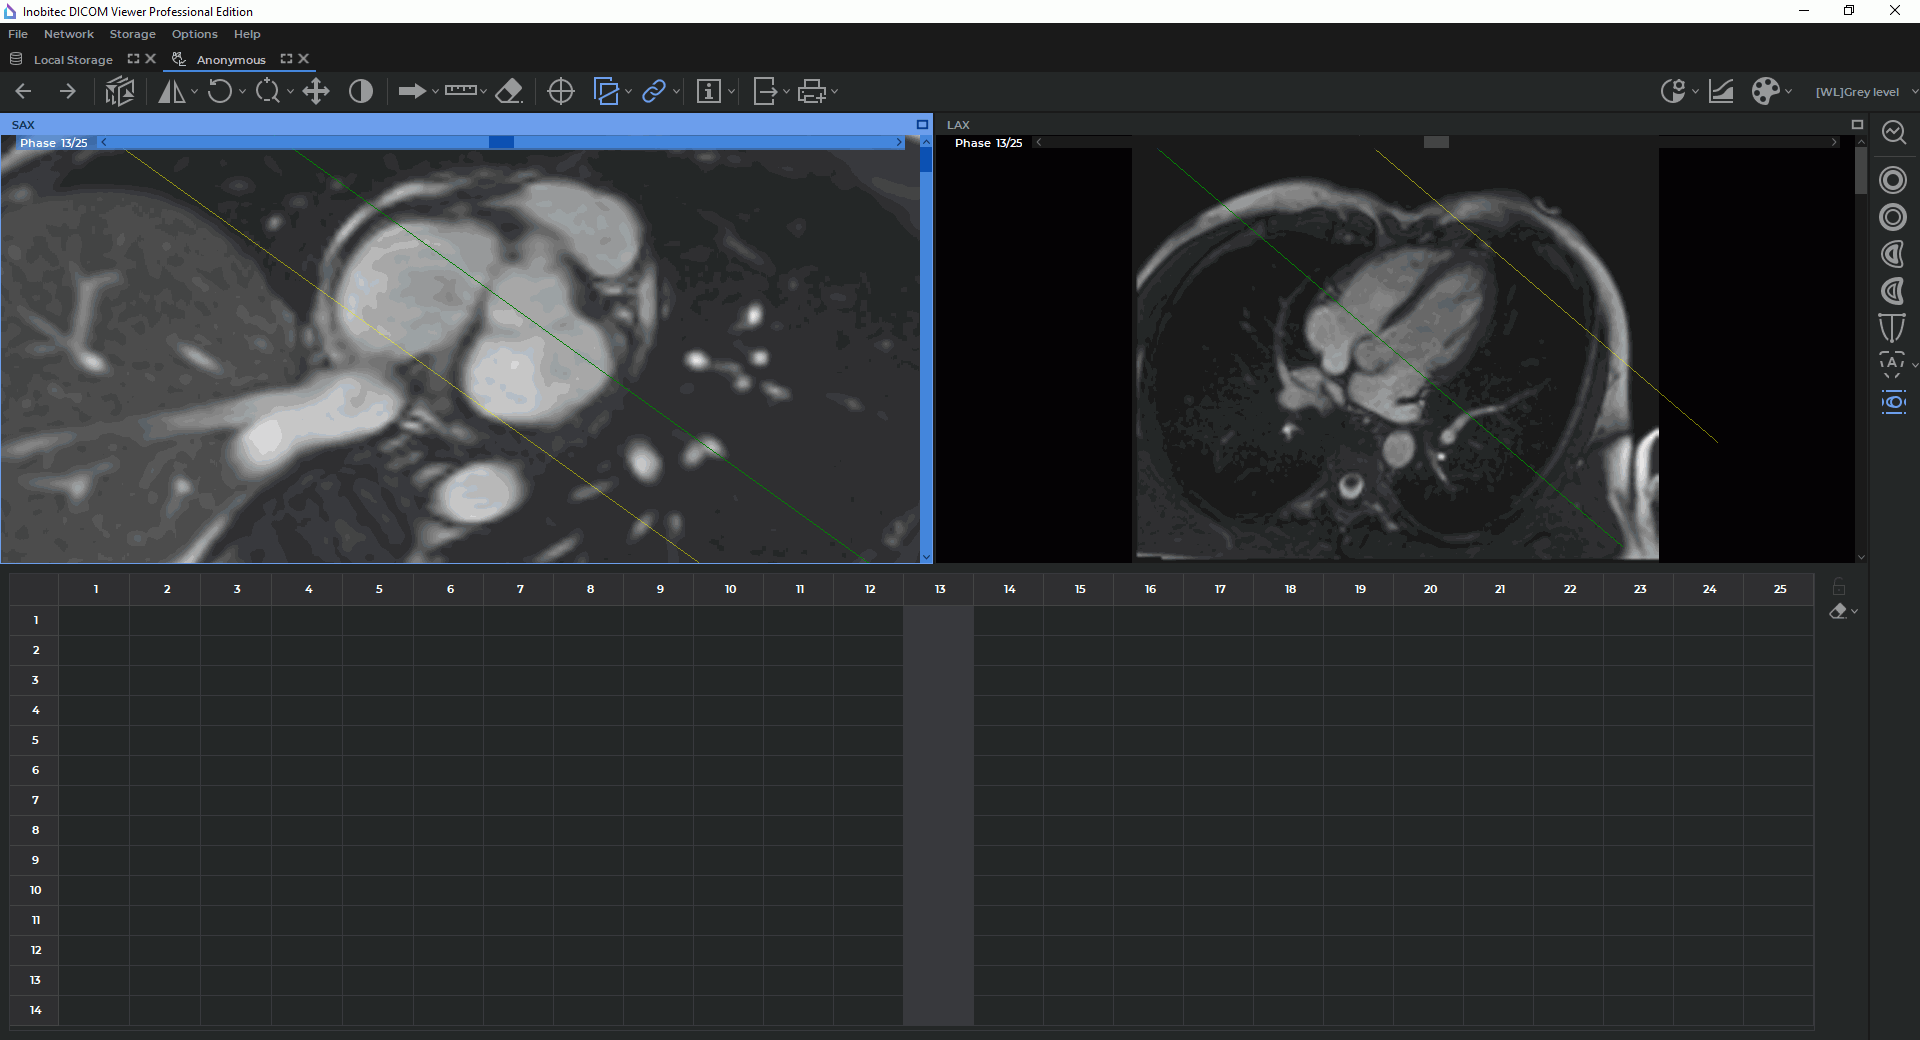

To escape the mode displaying all the slices for the current phase, click the right mouse button in the SAX window and disable the Multi-SAX arrangement option on the context menu. By default, the option is enabled and highlighted with blue on the menu. The SAX window in the Cardiac analysis tab will be displayed as shown in Fig. 8.3.

In this particular case, the SAX window shows only one slice for the current phase. The slices may be switched by moving the slider along the vertical scroll bar on the right-hand side of the window or on the contour panel.

To go back to the mode displaying all the slices for the current phase, click the right mouse button in the SAX window and enable the Multi-SAX arrangement option on the context menu.

The toolbar for cardiac function analysis is on the right-hand side of the Cardiac analysis (Fig. 8.3).